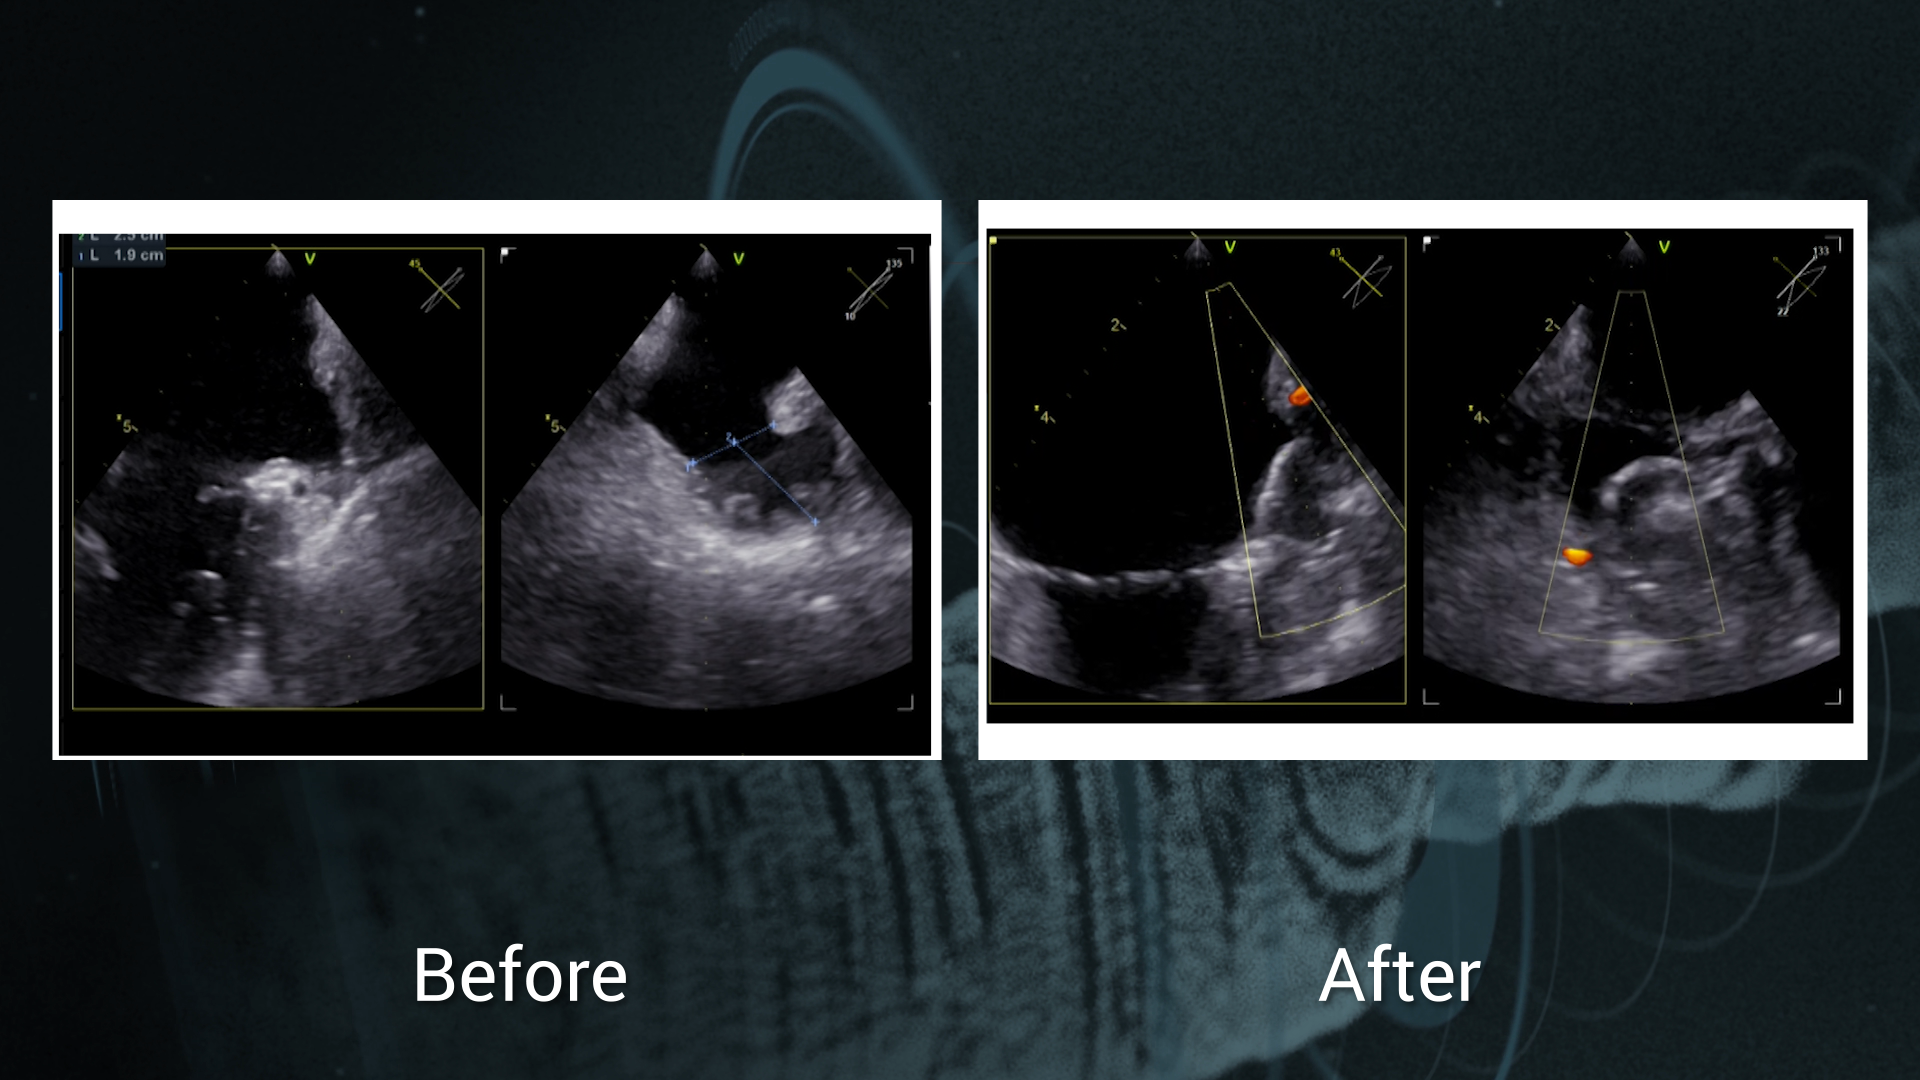

WATCHMAN FLX™ in complex patients: the benefits of the new implantation technique